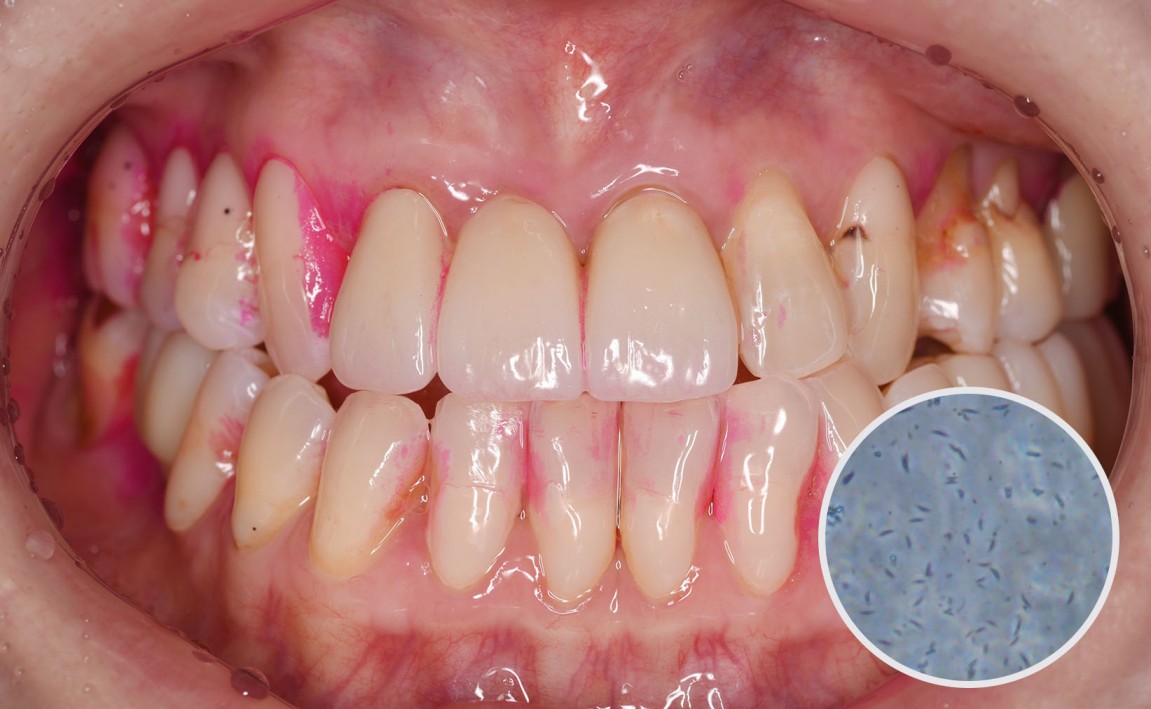

후.jpg

치료후 : 2023-12-05